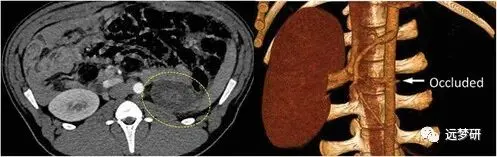

Embolization

In article number 2106865, Fiorenzo Omenetto, Rahmi Oklu, and co-workers demonstrate a silk embolic material (represented in yellow) being released from a catheter and occluding an artery. Therapeutics within the silk embolic material (shown in blue) diffusing outside of the arterial wall achieve targeted drug delivery within the tissue parenchyma.

栓塞术

在第 2106865 号文章中,Fiorenzo Omenetto、Rahmi Oklu 及其同事演示了丝栓塞材料(以黄色表示)从导管中释放并闭塞动脉。 丝栓塞材料(以蓝色显示)内的治疗药物扩散到动脉壁外,实现组织实质内的靶向药物输送。